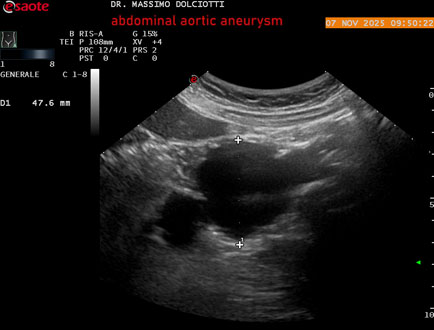

Data inserimento: 11/11/2025

Ecografia del: 07/11/2025

Strumento: Esaote MyLab Eight

Sonda: Convex Multifrequenza 1-8 MHz

Età Paziente: M 60 anni

Motivazione dell'esame: follow up per aneurisma dell'aorta addominale.

Commento all'esame: le immagini ed il video documentano la presenza dell'aneurisma dell'aorta addominale sotto-renale, con diametro antero-posteriore massimo documentato di 47 / 48 mm.

Conclusioni: aneurisma dell'aorta addominale in follow up (abdominal aortic aneurysm follow-up).

Presentazione: Dr. Massimo Dolciotti - Ancona